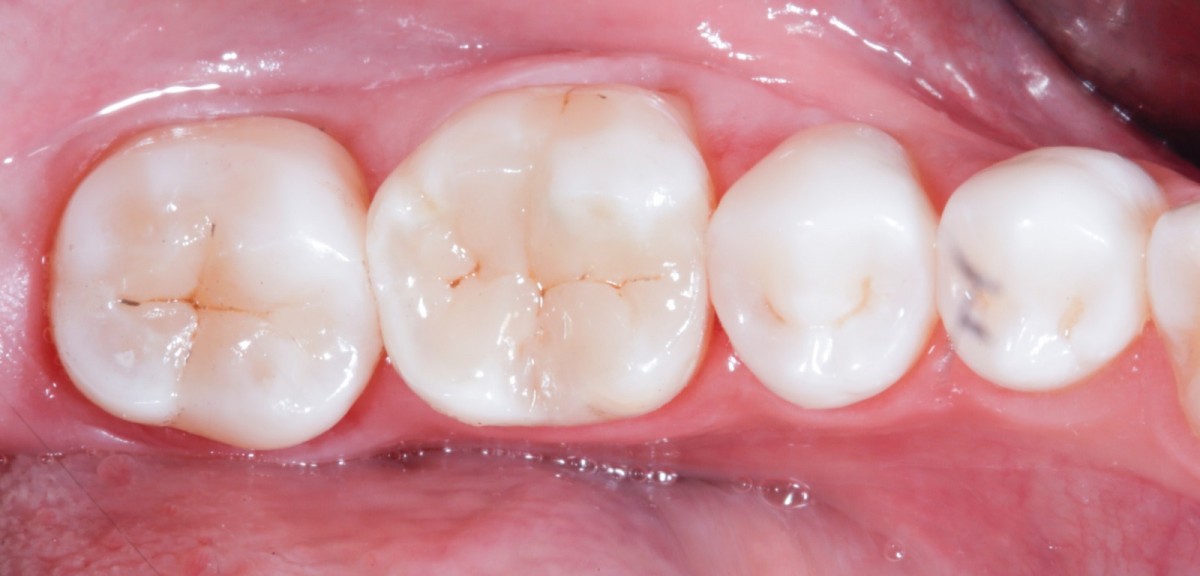

During the visit, consisting of the physical examination and instrumental examinations such as radiographs bitewings, thermal tests and compression tests (to exclude the presence of typical symptoms of a crack) at the level of the fourth quadrant, she has: amalgam restoration on dental element 4.6 associated with primary mesial caries and primary occlusal caries on 4.7.

The quadrant is rehabilitated through direct composite procedures.